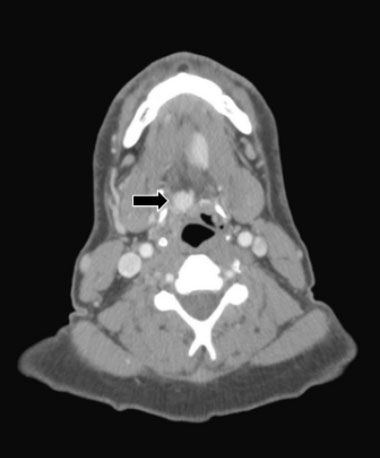

A 46-year-old male with a past medical history of hypothyroidism and cannabis use disorder presented to his primary care physician with a globus sensation and left cervical lymphadenopathy for two weeks. A computed tomography (CT) scan of the neck with contrast identified three high attenuation areas: the first in the midline floor of the mouth extending posteriorly to the base of the tongue (1.5 × 2.2 cm) (Figure 1), the second at the base of the tongue (1.4 × 1.8 × 3.0 cm) (Figure 2), and the third in the midline of the neck just beneath the hyoid bone (1.3 cm) (Figure 3). Thyroid tissue was not identified in the orthotopic location (Figure 4). A follow-up thyroid uptake and scan confirmed that each of these high attenuation areas was also iodine avid, consistent with thyroid tissue (Figure 5). Notably, there was no uptake in the normal orthotopic thyroid location.

Figure 1: Ectopic thyroid tissue located on the midline floor of the mouth extending posteriorly to the base of the tongue (1.5 × 2.2 cm).

In the reported cases of triple ectopic thyroid, the most common locations were the lingual (88%) and suprahyoid (88%) regions [1],[2],[3],[4],[5],[6],[7]. Less common locations included the infrahyoid (50%), pre-tracheal (25%), and cricoid cartilage (13%) areas [1],[2],[3],[4],[5],[6],[7]. Lastly, one patient only had ectopic thyroid lateral to the orthotopic thyroid [8]. In addition to lingual (Figure 1) and infrahyoid (Figure 2) areas, our patient had ectopic thyroid in the midline mouth (Figure 3) which has not previously been described and would seem quite unusual given the embryological pathway in normal thyroid development.